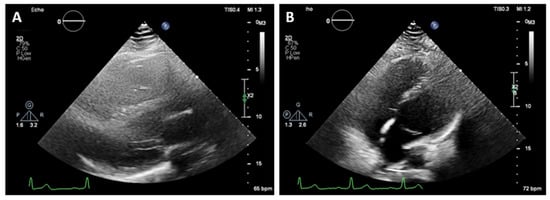

On 2D transthoracic echocardiography (TTE), an unusual heart position was noted with poor image quality from the standard acoustic windows. The parasternal long axis view gave the impression of right ventricular dilatation. An exaggerated motion of the left ventricular posterior wall was noted with hyperechogenic space behind it, which initially has been thought to be pericardium. The left ventricular apex was displaced laterally and posteriorly and was impossible to be visualized from the standard apical views (Figure 2). The apex was better demonstrated when the patient was not in left lateral but in supine position. The findings raised the suspicion of the atrial septal defect, and the patient was referred for CMR for further evaluation.

Figure 2. Two-dimensional transthoracic echocardiography. (A)—Parasternal long axis view gave the impression of right ventricular dilatation. Hyperechogenic space behind left ventricular posterior wall. Poor image quality. (B)—It was impossible to visualize the apex of the heart from the standard apical views in left lateral position.

In patients with CAP, the history and physical examination are often nonspecific and with no role in making the diagnosis. The ECG is usually normal in small or partial defects. In cases with complete pericardial absence, some typical findings include right axis deviation, complete or incomplete right bundle block and sinus bradycardia induced by vagal stimulation [7]. In these cases, chronic lung disease, congenital interventricular and interatrial septal defects with hemodynamically significant shunts should be considered. Echocardiography is also not characteristic, but some findings may raise the clinical suspicion of this diagnosis. They include unusual acoustic windows due to the abnormal heart position, right ventricle dilatation, cardiac hypermobility, “teardrop” appearance, and paradoxical motion of the interventricular septum [8]. In our case, a dilated right ventricle was registered at TTE, and in the presence of atrial septal defect (ASD), we referred the patient for CMR. Our differential diagnosis was for a significant left–right shunt. Chest X-ray finding in complete pericardial absence is known as “Snoopy sign” and include combination of levoposition of the heart, elongation and flattening of the left heart border, radiolucency between the pulmonary artery and aorta due to interposition of lung tissue and loss of the right heart border [7]. In the past, a diagnostic left pneumothorax has been used to confirm the diagnosis showing pneumopericardium [9]. Nowadays, the imaging modalities of choice for detecting pericardial absence are computed tomography and cardiac magnetic resonance. Since they are not affected by the acoustic window, they have a better sensitivity in identifying the levoposition of the heart and lung interposition in the aorto-pulmonary window and between the inferior cardiac border and the diaphragm. CMR is the gold standard for evaluating the cardiac anatomy, volumes and function and can demonstrate any functional abnormalities or regional bulging and herniation of the heart associated with pericardial agenesis. CT, on the other hand, has a greater spatial resolution and can be of help in identifying small defects [10,11].